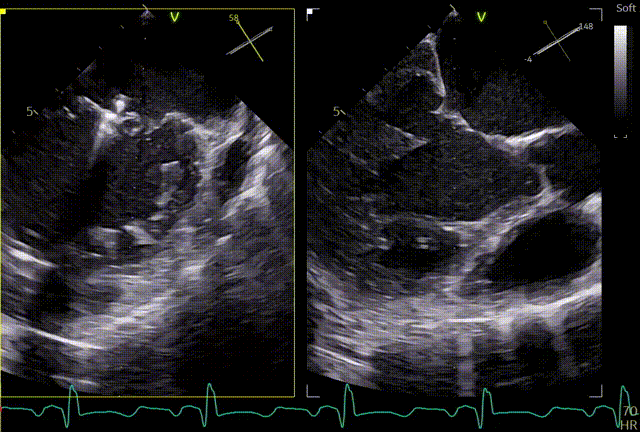

最终结果

术后肺静脉频谱

术后左房压